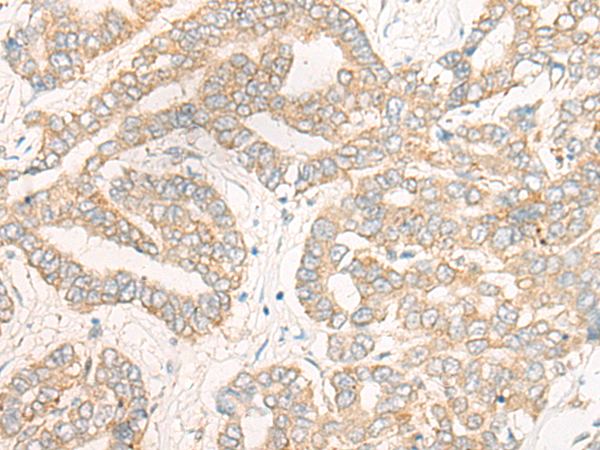

IHC positive control:

Human thyroid cancer;Human liver cancer

IHC Recommend dilution:

25-100